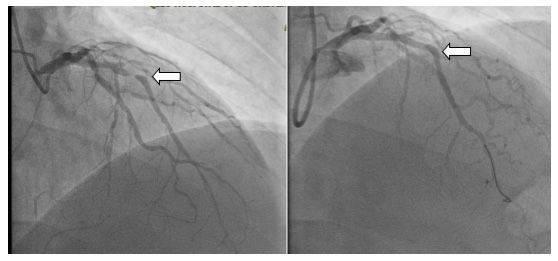

恭喜XINSORB可吸收支架在印尼取證!開啟國際化旅程!